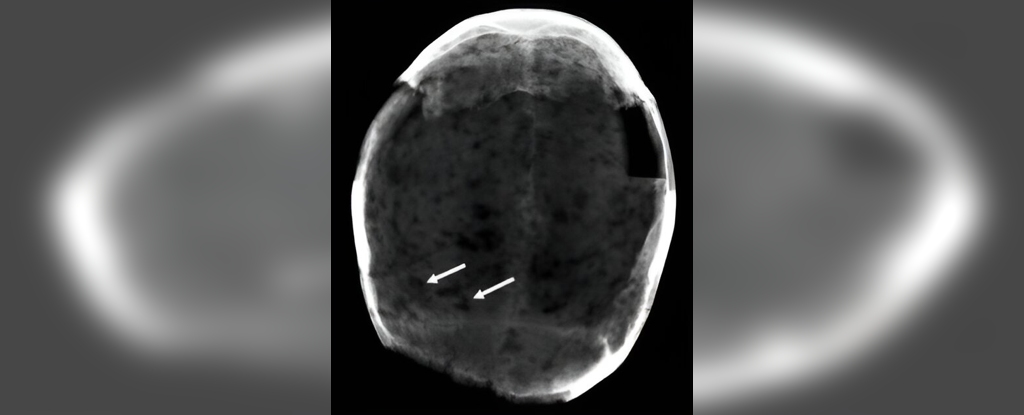

The cocaine molecules were found in the brain tissue of a male of 30 to 45 years of age, who had signs of tertiary syphilis on his cranium, and also in a brain that was no longer attached to its skeleton, meaning it could not be further identified.